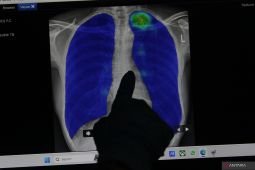

Dokter: Mitos seputar paru-paru basah

Dokter spesialis bedah toraks kardiak dan vaskular dari RSUP Fatmawati Jakarta meluruskan beberapa mitos seputar paru-paru basah, termasuk mitos yang mengaitkan kebiasaan tidur di lantai dan menggunakan kipas angin …